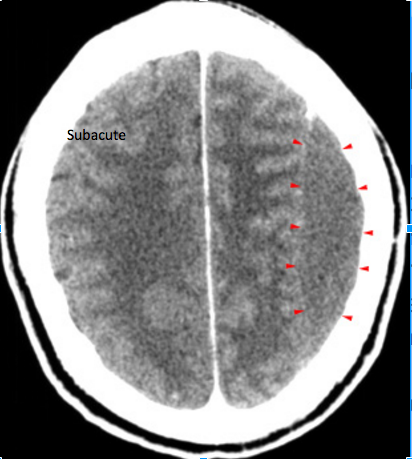

Subacute subdural hematoma (arrowheads). Whats important to note about this CT?

Note the compression of

gray and white matter in the left hemisphere due to the mass effect.